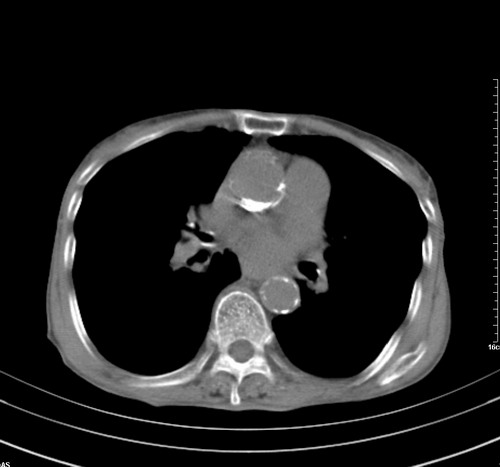

病人,女,79岁,主要因腹疼二月入院,彩超,肝,胆,脾,未见异常,胸透上消化道造影未见异常,化验白细胞增高,内科医生让做胸部ct检查,因为熟人多做了腹部(外科会诊考虑胆囊炎).现ct片如下请假各位战友.

中后纵隔占位,气管、食道受压、变形、移位。恶性可能性大。

考虑:中后纵隔转移瘤可能性大,主动脉硬化。

中后纵隔占位, 考虑:转移瘤不除外.

1 气管旁、隆突下淋巴结明显肿大,肝左叶外侧段低密影,都考虑转移。

纵隔淋巴结肿大,考虑转移而来

肺癌,纵隔淋巴结转移,肝左叶病变考虑为转移病灶。

中后纵隔转移瘤可能性大,主动脉硬化。

后中纵隔团块影,伴气管、食道受压移位,首先考虑转移瘤,肝s5段低密度灶。建议增强检查,另外其结肠是否有问题请提供,右肺部分肺叶局限含气增多,考虑局限肺气肿。

建议强化检查,考虑纵隔型肺癌,小细胞可能性大。

后中纵隔团块影,伴气管、食道受压移位,首先考虑转移瘤,肝表现同11773。

后中纵隔淋巴结肿大,首先考虑转移瘤。